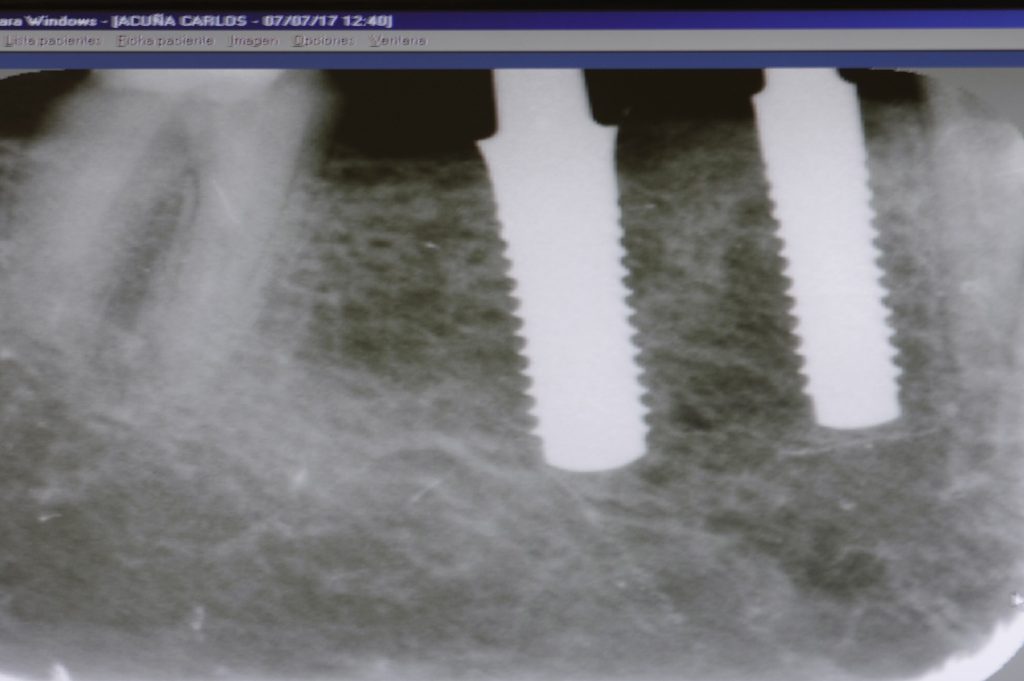

Autores: PRÓLOGO Asimismo, desde el punto de vista pedagógico, el profesional nobel en la materia tiene a su alcance la posibilidad de corregir cualquier posición implantaría en el ordenador, planear los provisionales y plasmarlos en la bio réplica antes de tocar al paciente a operar. Todos estos razonamientos nos llevan a presentar un caso de condiciones muy favorables para poner en práctica estos métodos como primer acercamiento a una Odontología Digital de alta calidad, con medios informáticos, que ya están presentes en la profesión de hoy en día, y será la protagonista única del futuro. Por otro lado, después de numerosos estudios que nos llevan a plantear el “gap” entre implante y pilar(abuttment), como principal responsable de la periimplantitis dado que la microbiota presente en el mismo es imposible de limpiar y en su presencia la cortical ósea reacciona reabsorbiéndose, nos ha llevado a utilizar implantes monobloc ya que los ejes implantarios y protéticos coincidían, y nos permitían su uso. Además, el circonio, ha mostrado a la luz de estudios muy recientes, una preservación y adhesión de los tejidos blandos superiores al titanio, tanto en su tratamiento de superficie de la rosca como a nivel gingival. DESARROLLO Paciente varón de 68 años, con antecedentes de radio/quimioterapia cinco años antes, con Rehabilitación Oral de los cuatro cuadrantes, con una Oclusión Mutuamente Compartida conservada, (REF.8) la que fracasa en el cuadrante 4, 19 años después. El mismo presentaba un puente de porcelana sobre circonio con pilares en 44 y 47, reemplazando el edentulismo de 45 y 46. Se produce la fractura del PM del 44, y ante una endodoncia antigua y corta, se decide implantar las zonas edéntulas, conservando temporariamente los pilares, hasta producida la oseointegración, para entonces también exodonciar el 44. DIAGNÓSTICO Tomamos impresiones del maxilar antagonista, Arco Facial Estático y realizamos montaje del mismo mediante la sistemática ARTEX. Producimos la relajación del músculo Pterigoideo Externo, para obtener la ORC (Oclusión en Relación Céntrica) mediante el método de Laminillas de Long, basado en el concepto de INERVACIÓN RECÍPROCA. Esto nos permitirá montar el maxilar inferior, tanto en su forma de: La primera para practicar la cirugía guiada y comprobar su eficacia, y el modelo de yeso para ser escaneado y confeccionar la GUÍA QUIRÚRGICA. La Biorréplica la obtenemos transformando los archivos DICOM que nos da el CBCT en archivos STL, y a partir de ellos, mediante una tecnología de PROTOTIPADO RÁPIDO, la obtención de un objeto físico en 3D a través de la aglutinación selectiva de una sucesión de capas de polvo. Procedemos a montar la biorrèplica y el modelo de yeso del caso. Podemos verificar la exactitud de las medidas del hueso residual en la bio réplica y compararlas con el scanner. Arrojando un resultado de 8,5 mm de cortical externa a cortical externa. Pudiendo también medir la distancia hasta el dentario. y comparar gracias a la ventana lateral de la biorréplica Dándonos 22mm de distancia. Con lo cual deducimos que implantes de 4,1mm por 12 mm serán perfectamente rodeados de hueso. Medimos también la distancia desde oclusal del antagonista, hasta el hueso desnudo. Lo mismo que, mediante la utilización de la guía radiológica, con un material radiolúcido colocado en gingival de la misma, podemos medir la altura de la encía. Con lo cual podemos calcular la altura del pilar. Es entonces cuando con el programa COC Diagnostix se realiza la programación final: Obteniendo no solo la ubicación, largo, ancho y ángulo de los implantes sino también los provisionales mediante CAD CAM. Ya entonces podemos hacer la práctica quirúrgica en la bio réplica, mediante la guía quirúrgica, instalando los implantes de prueba que no serán los de circonio, ya que la casa no cuenta con ellos, pero si otros de las mismas dimensiones. TRATAMIENTO Entramos ya en la cirugía propiamente dicha. Antisepsia de la zona a operar y zonas anexas. Comprobación del perfecto ajuste e inmovilidad de la G.Q. en boca durante la cirugía. Marcado de la encía y perforación de la cortical. Visión a través de la Guía de la mínima intervención anterior. Comprobación sin Guía. Incisión mínima mesio distal, para apartar y conservar encía queratinizada. Secuencia de drills, perforando a profundidad requerida Observación del Mínimo Trauma Implantes Strauman de Zirconio Monoblock en blíster y montádo en contrángulo reductor. Instalación controlando torque con contrángulo reductor. Comprobación clínica. Comprobación Radiográfica y con Guía. Toma de impresiones, y armado de modelos con técnicas de pasividad protética. Montaje. Resultado de las provisionales ejecutadas por CAD CAM Al no estar conformes con el resultado decidimos desechar dichas provisorias y optar por repetirlas. Nuevas provisorias realizadas mediante encerado convencional. Estado de los tejidos blandos. Provisorias en boca. Oclusión de Estímulo Inmediato. Ref.10: Carga inmediata .Alberto y Diego Bechelli. Comprobación mediante CBCT post operatorio Componentes del equipo (En la próxima presentación, mostraremos las coronas definitivas de porcelana sobre circonio, y la desoclusión provocada por una OCLUSIÓN MUTUAMENTE COMPARTIDA, sobre estos implantes y otros seis mas) REFERENCIAS

Realizamos previamente una Rx periapical Dígora (radiovisiografía) y un CBCT (TAC de haz de cono) con férula radiológica, marcando ambas raíces del 46 y la raíz del 45.

Mas adelante, y por cuestiones de conveniencia protética, el implante instalado del premolar será de 3,3 mm.

FIG:55

FIG:56

FIG:57

FIG:58